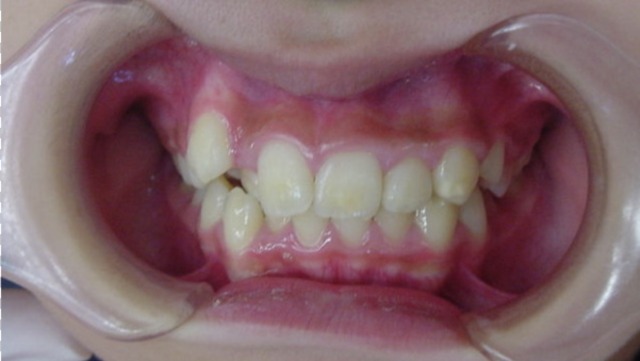

After

| 症状 | 上顎前歯の右側転位のために、右側2番の舌側転位と右側3番(犬歯)の萌出スペースなし。 |

| 処置内容 | 1期治療 プレート拡大装置 2期治療 マルチブラケット装置(右上7番抜歯してそこに右上8番親知らずを誘導した。) |

| デメリット・院長コメント | 永久歯を抜かない治療のデメリットは、治療期間が長いことです。ただし、その後の人生の長さを考えると、健全な小臼歯を2本または4本抜歯の矯正治療よりも、はるかにメリットがあるといえます。また、アーチが小さくならないので、舌が後ろに押し込まれないためいびき防止につながり睡眠の質の向上にもつながります。 |